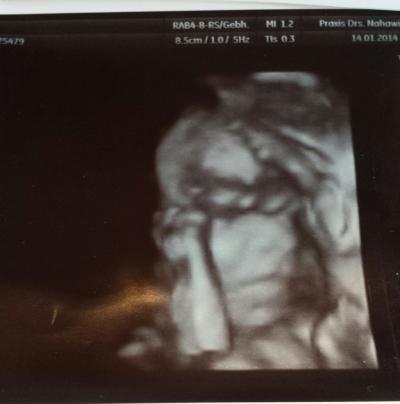

Hey Maedels, wir hatten heute das 2. Screening und es war echt wundervoll. Mein FA hat Normal & 3D geschallt.. hab 4 Bilder bekommen in 3D umsonst. Herzchen haben wir schlagen gehoert und die kleine Maus ist gesund also alles suppi :) 440 gramm - 26 cm bei 20+6 :) Nabelschnur direkt am Kopf und sie spielt damit(siehe Foto) Jedoch zeigt der Ultraschall immer 1 woche mehr an also heute 21 + 5, mein FA meinte aber das aendern wir jetzt nicht mehr das wird sich dann zeigen wann sie kommt :) tiefsitzende plazenta ist auch hoch gewachsen, Mumu frei! ;) also sehr positiv

Das Bild ist ja suuuuuuper Man erkennt ja total viel. Eine kleine Nase und den Mund... Toll. Schön das es der kleinen Maus gut geht.